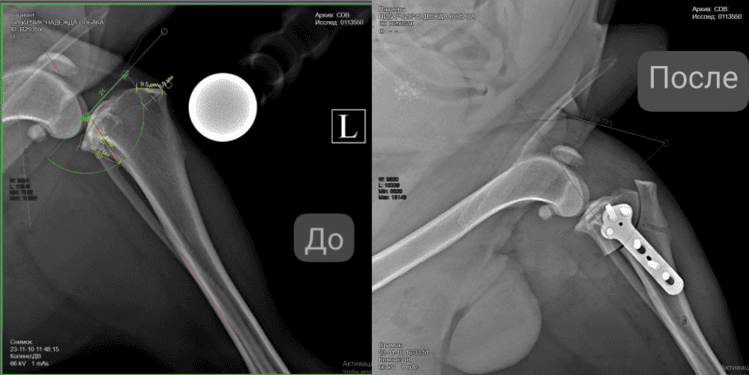

Суть операции заключается в изменении угла наклона суставной поверхности большеберцовой кости. Хирург делает разрез, корректирует положение костного фрагмента и фиксирует его пластинами и винтами. Такая коррекция позволяет коленному суставу сохранять стабильность даже при отсутствии функции повреждённой связки.

Вмешательство проводится под общей анестезией. Перед операцией пациент проходит обязательное обследование: анализы крови и рентгенографию поражённого сустава.